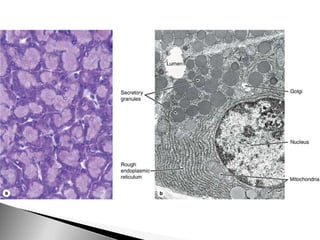

Acinos serosos del páncreas, gránulos en color rojo, tricrómico de Liisberg.